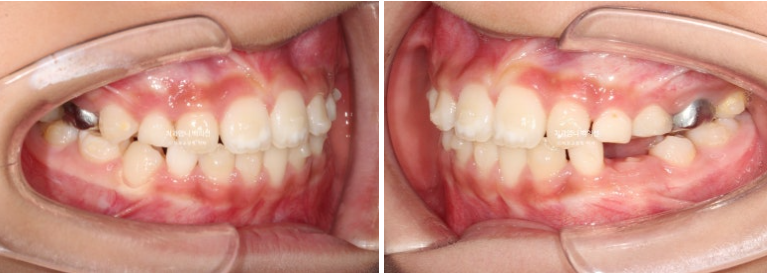

중심선이 많이 어긋나 있으며 파란화살표는 위아래가 거꾸로 물리는 반대교합입니다.

유치송곳니끼리 거꾸로 물리는 상태라 이 부분에 교합간섭이 있습니다.

윗니가 아랫니를 덮지 못하는 절단교합입니다.

악궁확장으로 파란 화살표 반대교합이 해소가 되면서 교합간섭이 사라졌습니다.

교합간섭이 사라지니 턱이 제 위치를 찾으며 어긋났던 앞니 중심선도 자연스레 맞아졌습니다.

윗니가 아랫니를 정상적으로 덮지 못하는 절단교합 이었으나, 3급 고무줄로 적절한 앞니교합을 형성했습니다.